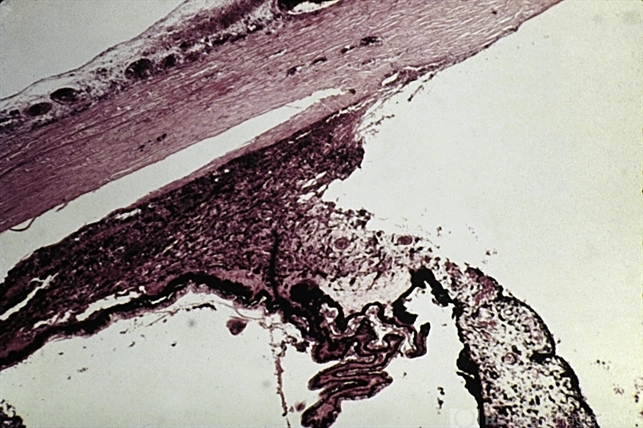

- ciliary, trauma

- Traumatic tear in the face of the ciliary body.